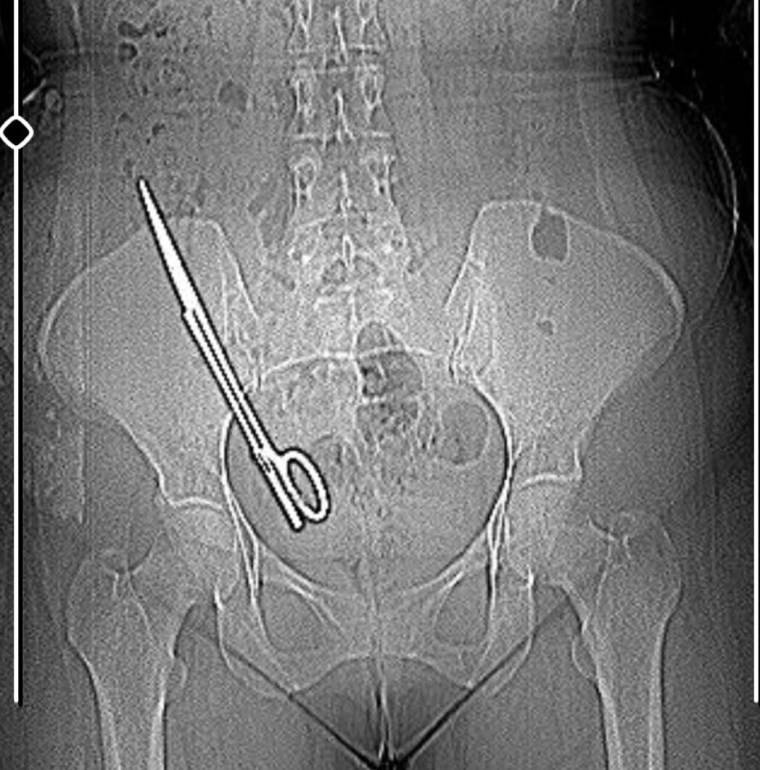

Burada yapılan tetkiklerde Kala’nın karnında 16 santimetre uzunluğunda makas olduğu tespit edildi. Ameliyatla karnındaki makas çıkarılıp salığına kavuşan Fatma Kala, hastaneden çıktıktan sonra avukatı aracılığıyla 7 yıl önce ameliyatı gerçekleştiren doktor Koray Ş. hakkında Kahramanmaraş Cumhuriyet Başsavcılığı’na suç duyurusunda bulundu.

Baş ağrısı şikayetiyle gittiği hastanede doktorların 'Karnında makas var' deyince şoke olduğunu belirten Fatma Kala, 2017 yılında kist ameliyatı olduktan sonra iç kanama geçirdiğini ve tekrar ameliyata alındığını, makasın da o ameliyatta unutulduğunu söyledi. Karnında makas varken küçük çocuğu ile birçok defa MR odasına girdiğini belirten Kala, “Bundan 7 yıl önce özel bir hastanede ameliyat oldum. O günün gecesinde tekrar iç kanama geçiriyorum ve ikinci ameliyatımı oluyorum. Bu ameliyatta maalesef ameliyat olan bölgemde ameliyat makası unutuyorlar ve biz bunu 7 sonra öğreniyoruz. Baş ağrısından dolayı hastaneye gittik. Hastanede doktorumuz MR'a girmem gerektiğini söyledi. Ben MR teknisyenine daha önce çocukla beraber MR odasına girdiğimde benim sağ tarafımda çekme olduğunu söyledim. Teknisyen bana 'Bu şekilde seni MR'a alamam, çok tehlikeli. Acilen ameliyat olduğun doktoru bul' dedi. Doktorumuz bizi hemen röntgene aldı. Röntgende bir yabancı cisim görmüş ama bize söylemedi, ‘Daha önceki ameliyatından dolayı bir komplikasyon oluşmuş. Seni ameliyat edip dedi o komplikasyonu ortadan kaldırmam gerekiyor’ dedi. Biz doktorun telaşlı tavrından şüphelendik. Eşimle birlikte tıp fakültesine gittik. Oradaki acil doktorlarına başımızdan geçen olayı anlattık. Onlar beni röntgene soktu. Oradan ilaçlı tomografiye girince daha önceki ameliyatımda bırakılan makas orada görüldü. Genel cerrahi bölümünde bu makas çıkarıldı'' diye konuştu.